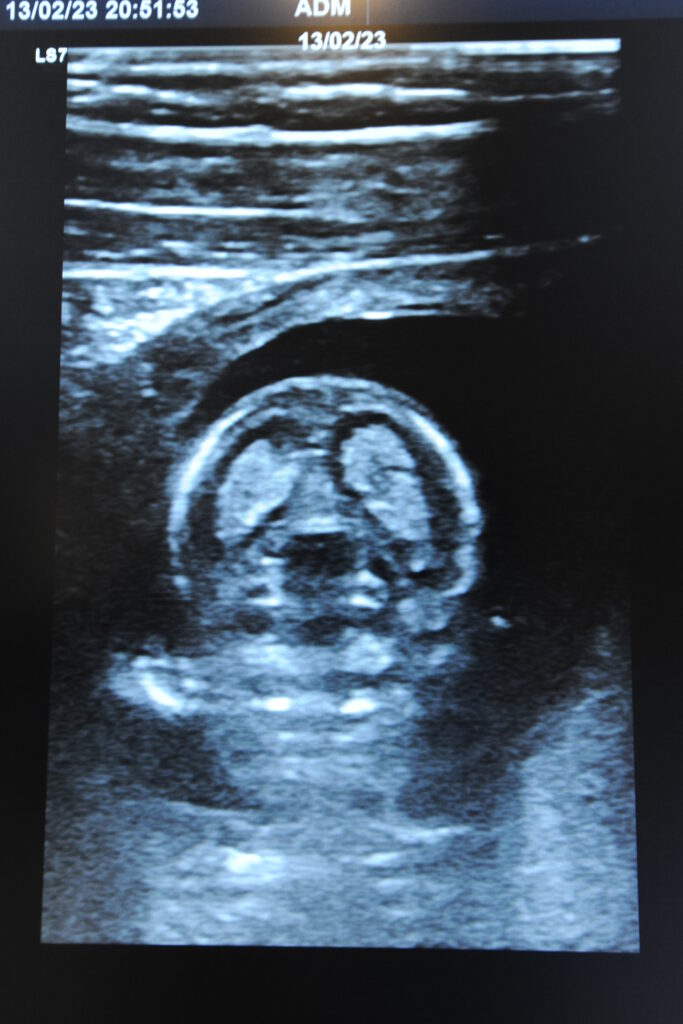

– Ultraschalluntersuchungen (Echokardiografie) von Herz,

Bauch-

- Komplett-Check: (ausgiebige Anamnese, körperliche Untersuchung, Hautkrebsscreening, Stuhluntersuchung auf Mikroblutungen, Urinuntersuchung, grosse Blutuntersuchung, Ultraschall vom Bauch, Herz, hirnversorgende Gefäße, Schilddrüse, Lungenfunktionsuntersuchung, EKG, ggf. Belastungs EKG)